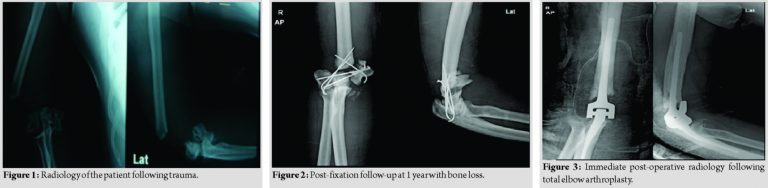

A 51-year-old male presented to our institute with a history of injury to right elbow (sideswipe injury). On clinical and radiological examination, it was open Grade III B fracture of distal humerus with bone loss (Fig. 1). He was operated with wound debridement and initial temporary fixation with k-wires and later soft-tissue reconstruction.

One year later, the patient did not show any signs of infection and was essentially flail limb, with a limited range of motion (passive range of motion 40° 70°). Radiology revealed the non-union of condylar fragments with bone loss (Fig. 2). We advised TEA as a treatment option as he was a sedentary office worker with deliberate discussion about the advantages as well as long-term prognosis.

After routine evaluation for surgery, the elbow was approached in lateral position through the previous scar posteriorly. Triceps were reflected off subperiosteally [1]. Humerus and ulna prepared, there were no condyles per say only distal humerus. After cementing a modular Coonrad-Murray semi-constrained prosthesis implanted. Triceps sutured back with no. 5 Ethibond. Soft padding dressing done (Fig. 3).